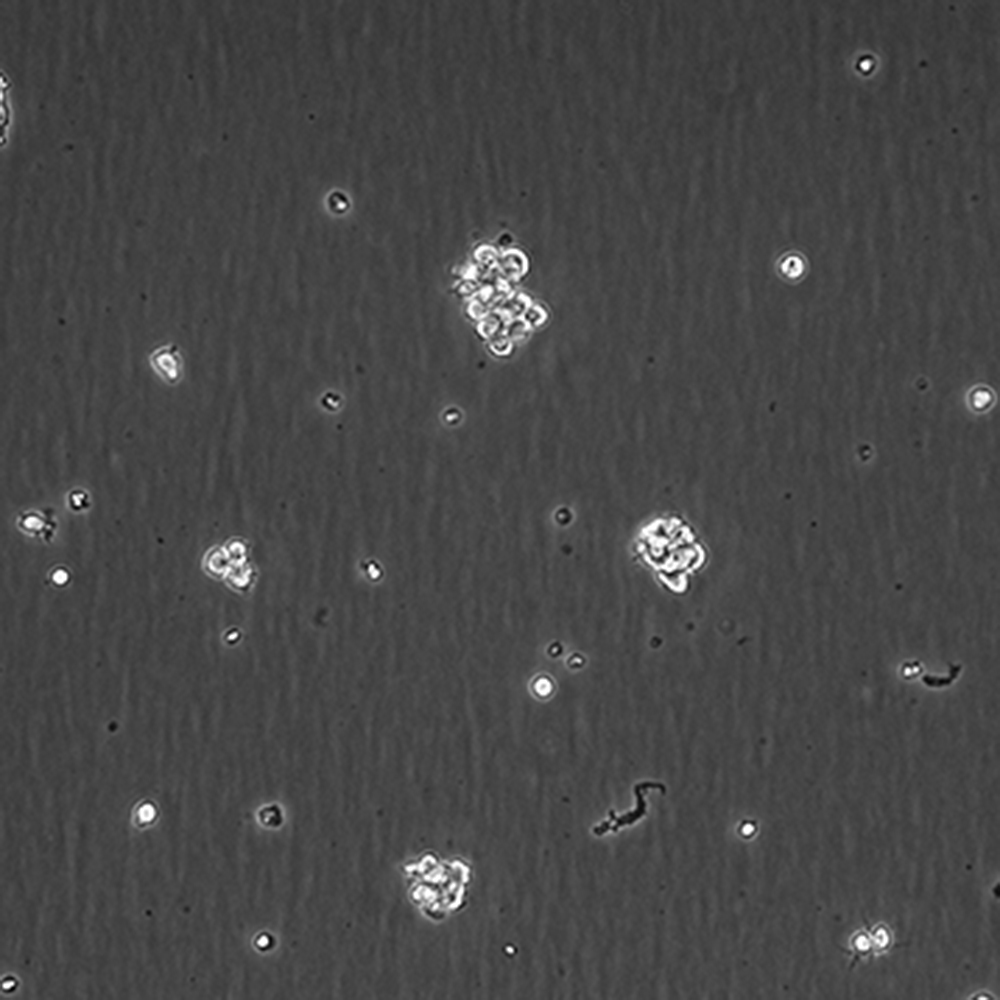

產品名稱 SU-DHL-2

中文名稱 人間變性大細胞淋巴瘤細胞

組織來源 間變性大細胞淋巴瘤;胸腔積液轉移;女性

生長特性 懸浮

培養基 1640,90%;FBS,10%;雙抗。

傳代方法 Maintain cultures at a cell concentraion between between 1 X 10(5) and 1 X 10(6) viable cells/ml.

培養條件 Atmosphere: Air, 95%; CO2, 5%。Temperature: 37℃